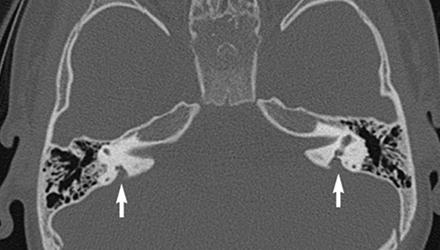

SLC26A4基因定位于人類染色體7q31,SLC26A4基因和大前庭導(dǎo)水管綜合征相關(guān)突變位點的發(fā)現(xiàn),證實SLC26A4是大前庭導(dǎo)水管綜合征的責(zé)任基因。

我們平時提到的“一巴掌打聾”、“一跤摔聾”其實都與SLC26A4基因突變有關(guān),絕大多數(shù)大前庭導(dǎo)水管綜合征都是SLC26A4基因突變?nèi)堑牡湣?/p>

SLC26A4基因編碼一種叫“Pendrin”的跨膜轉(zhuǎn)運蛋白,在機體離子成分平衡的維持中發(fā)揮重要作用。

在內(nèi)耳,Pendrin表達于內(nèi)淋巴管、內(nèi)淋巴囊、橢圓囊、球囊等處,異變的蛋白將對這些結(jié)構(gòu)的正常生理功能產(chǎn)生影響,引發(fā)聽損。

SLC26A4基因突變導(dǎo)致的大前庭導(dǎo)水管綜合征的典型表現(xiàn)為兒童時期的聽力損失,90%的患者為雙側(cè)性,聽力損失程度不一,可表現(xiàn)為接近正常或重-極重度。

病程可為穩(wěn)定性、進行性或波動性,聽力可逐步下降至全聾;跌倒、撞擊等行為或無外界影響都可能引發(fā)聽力的下降。